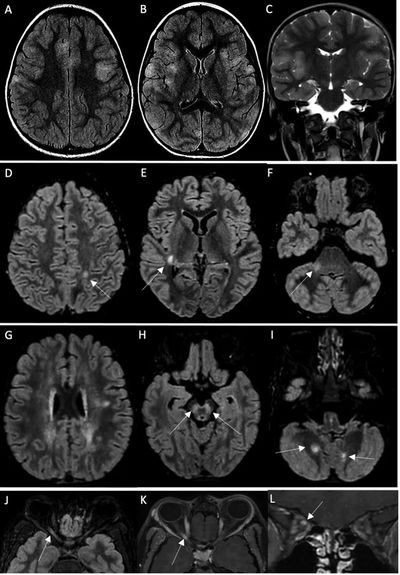

19名患者中有14名MRI异常。4例MRI显示ADEM伴有多灶性脑损伤,1例伴有视神经炎;3例显示胼胝体细胞毒性病变(CLOCC综合征),胼胝体压部扩散受限,T2-FLAIR高信号,2例小脑炎;1例分别显示孤立性视神经炎、孤立性面神经炎和多发性神经炎。19例脊柱MRI中有5例异常:5例显示脊髓炎,其中3例与ADEM相关,1例为孤立性,1例与马尾神经根的对比增强相关。所有脊髓炎病例均显示超过3个椎体受累。